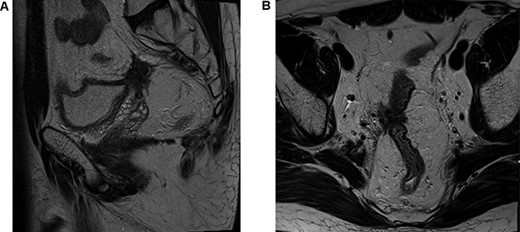

Postoperative histology demonstrated complete pathological response and an R0 resection (ypT0 N0(0/46) M0R0; Fig. 3). The patient proceeded to completion chemotherapy of 6 cycles of FOLFOX (folinic acid, fluorouracil and oxiliplatin) at 6 weeks postoperatively. He was then entered into a formal surveillance programme.